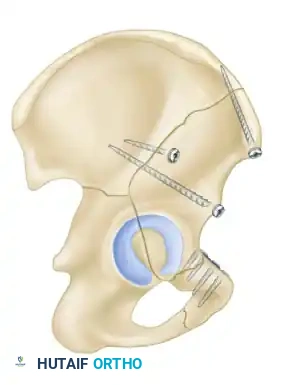

The Kocher-Langenbeck Approach

- Indications: Posterior wall, posterior column, and certain transverse fractures.

- Positioning: Prone or lateral decubitus. Prone positioning allows for easier reduction of the posterior column using gravity, while lateral positioning is preferred if the patient has severe pulmonary contusions or requires simultaneous access to the anterior column.

- Interval: The gluteus maximus is split in line with its fibers. The short external rotators (piriformis, obturator internus, gemelli) are tagged and released at their femoral insertions to expose the retroacetabular surface and the greater sciatic notch.

- Nerve Protection: The sciatic nerve must be identified and meticulously protected throughout the procedure. Keeping the hip extended and the knee flexed reduces tension on the nerve.

The Modified Stoppa Approach

- Indications: Medial displacement of the quadrilateral surface, anterior column fractures, and certain both-column fractures.

- Positioning: Supine.

- Technique: A transverse Pfannenstiel incision is made, and the surgeon works intrapelvically, deep to the rectus abdominis and along the pelvic brim. This approach provides direct visualization of the quadrilateral plate and allows for the application of medial buttress plates to prevent medial subluxation of the femoral head. It is frequently combined with a lateral window (from the ilioinguinal approach) for complete anterior column access.